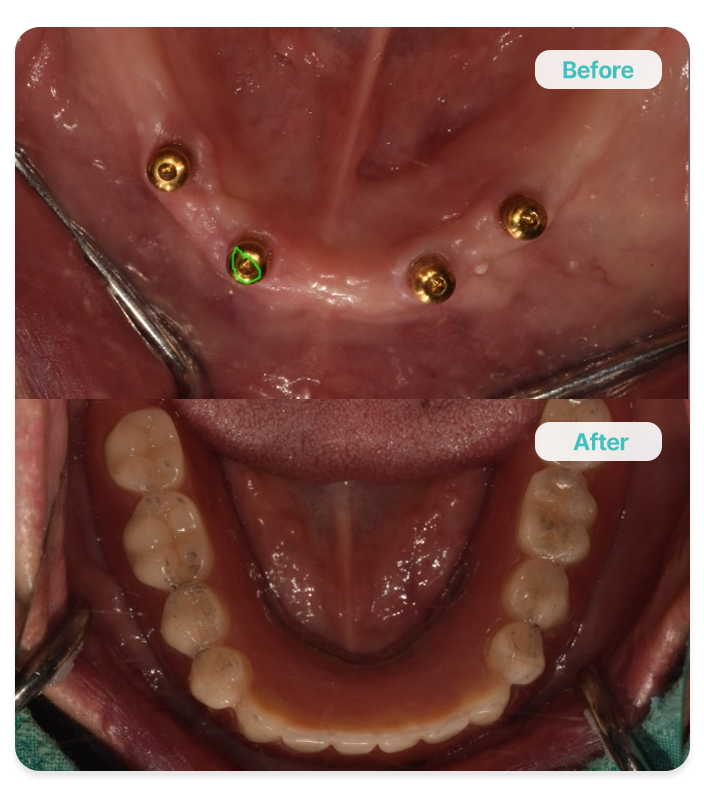

Implant-Supported Denture

틀니 지지 임플란트

소수의 임플란트를 식립하여 기존 틀니의 안정성을 높이고,

저작 효율 개선을 돕는 방식으로 틀니 고정력을

보완하는 치료입니다.

소수식립

고정력 향상

경제적인 비용으로 치료 가능